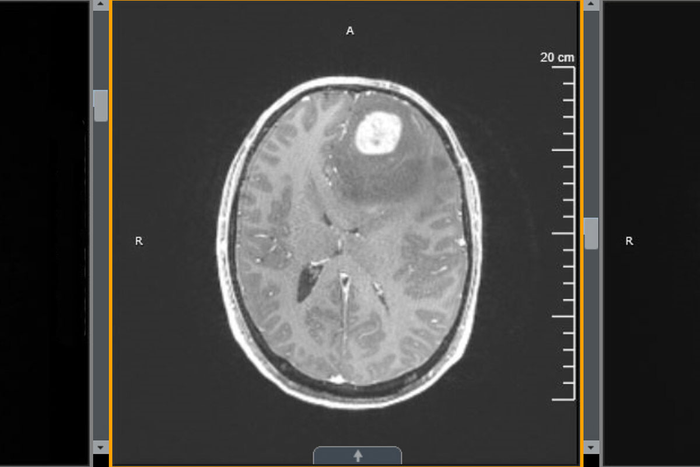

Boosting T cells improves survival in mice with glioblastoma

Glioblastoma, an aggressive cancer in the brain or spinal cord, has proven stubbornly resistant to newer immunotherapies. And radiation and chemotherapy, the standard treatment for glioblastoma, result in fewer than 10% of patients surviving longer than five years after diagnosis.

But a new study from researchers at Washington University School of Medicine in St. Louis shows that treatment with an immune-boosting protein called interleukin 7 (IL-7) in combination with radiation improves survival in mice with glioblastoma. The new mouse study shows that IL-7 increases the number of T cells in the tumor and other immune organs. Such immune cells can then attack the cancer cells and improve survival.